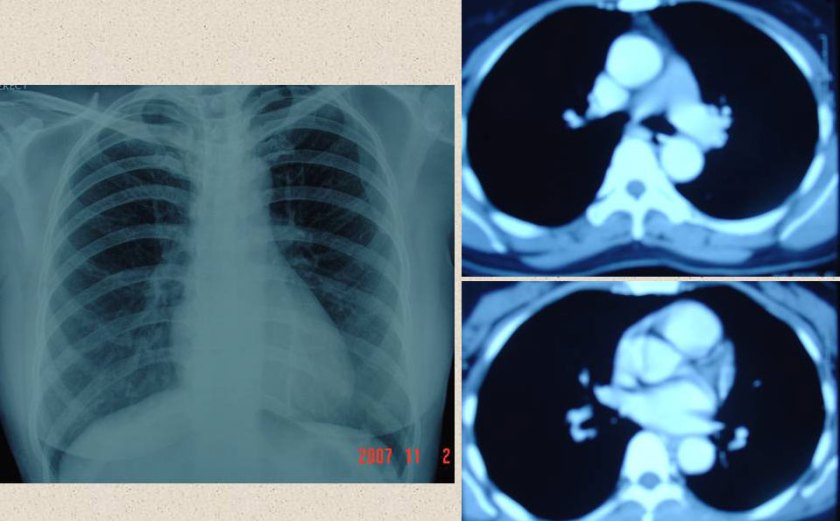

CT chest  21 June 2008

1. There is 2.7 cm right hilar mass suspicious for malignancy.

2. Probable post-obstructive pneumonitis of the right middle lobe.

3. There is a new 2.7 cm right adrenal mass consistent with metastasis.

4. Stable fibrosis at the lung apices.

PET scan 18 July 2008

1. Hypermetabolic right hilar mass is highly worrisome for malignancy.

2. Mildly hypermetabolic hilar and subcarinal lymph nodes still worrisome for lymph node metastasis.

3. Markedly hypermetabolic right renal mass.